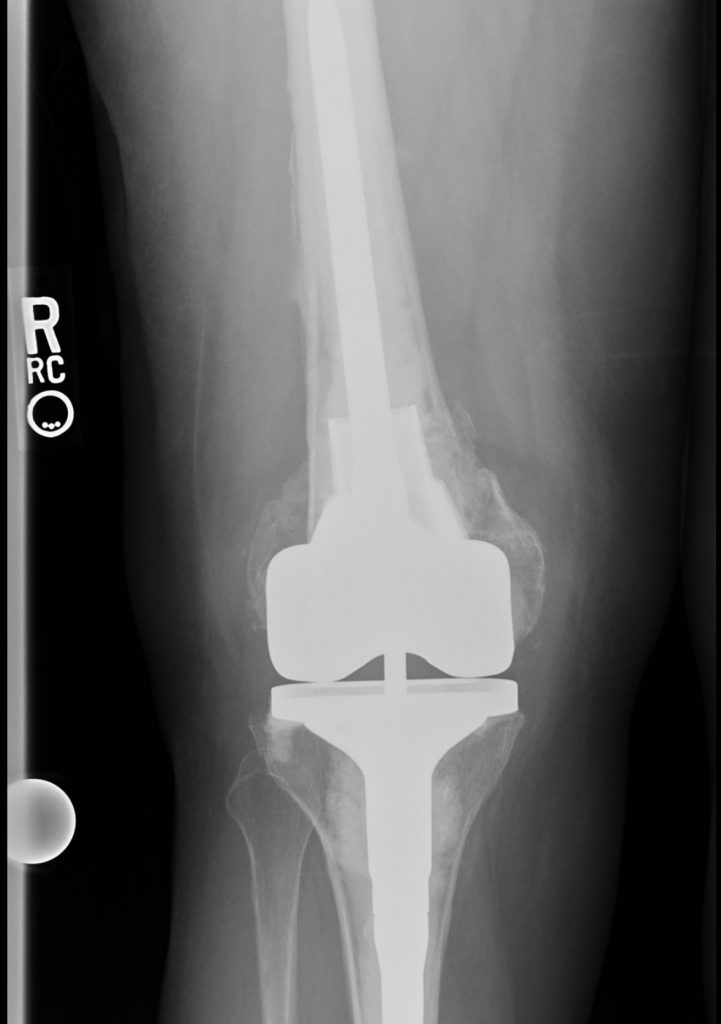

Over a year ago, I tripped and broke the base of my femur, requiring emergency surgery with plates and bolts to repair and set my leg. I was non-weight bearing for 10 weeks progressing to full weight bearing over several months. Seven months in my recovery, my kneecap dislocated by simply rolling over in bed, sending me to the hospital for sedated manipulation back into place. It happened two more times with ER visits, requiring me to wear a kneecap immobilizer 24/7. With this complication, CT scans were done which showed that my femur grew back at an angle and rotated which caused my lower let to jut out to the right. My kneecap had no channel to sit, forcing me to wear an immobilizer 24/7. Because my legs were deformed, walking short distances were difficult. The plan was to perform a distal femur replacement (removing the base of my femur) and a hinged knee replacement (last resort). I was referred to Dr. Gausden at HSS and after meeting her at my pre-op appt, she said I was too young to loosen the base of my femur and she would do her best to save my femur. With mere determination and over 6 hours of surgery, Dr. Gausden saved my femur and performed a total knee replacement. She was a miracle worker. I had the best experience at HSS with Dr. Gausden and her team. I can't thank Dr. Gausden enough for her skillset and determination to save my femur.

Elizabeth B. Gausden, MD, MPH

Hip and Knee Replacement Surgeon